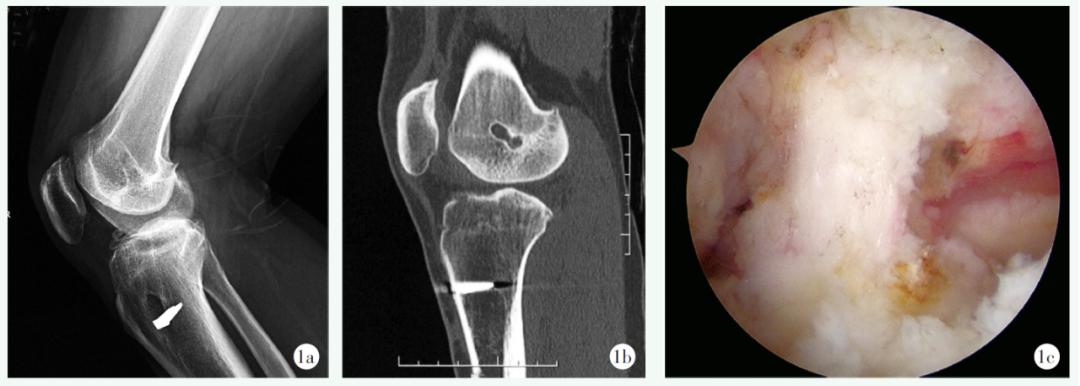

36例患者中,34例(94.44%)为初次进行翻修手术,1例(2.78%)为第二次进行翻修手术,1例(2.78%)为第三次进行翻修手术。33例(91.67%)患者初次重建术移植物使用了自体肌腱,2例(5.56%)使用了同种异体肌腱,1例(2.78%)使用了LARS人工韧带。5例患者合并其他韧带损伤,其中4例(11.11%)为内侧副韧带损伤,1例(2.78%)合并后交叉韧带损伤。共有23例患者同时存在半月板损伤,其中8例(22.22%)合并外侧半月板损伤并进行了修整;13例(36.11%)存在内侧半月板损伤,其中2例进行了内侧半月板切除;2例(5.67%)患者为双侧半月板损伤;5例患者既往病历未明确记录是否对半月板进行了处理。通过对标准化影像学资料进行评估,共有14例(38.89%)患者股骨隧道位置不佳(偏前)(图1a~1c),1例(2.78%)患者股骨、胫骨隧道位置均不佳,1例(2.78%)胫骨隧道位置不佳,17例(47.22%)隧道位置正常,3例(8.33%)患者因间隔时间过长或存在术后感染而无法明确确定骨道位置。对上述资料进行整合归纳,在患者初次ACL重建失败的因素中,19例(52.78%)为创伤导致的翻修;10例(27.78%)为单纯的技术原因;3例(8.33%)患者因生物学原因而翻修;7例为组合因素,其中6例(16.67%)同时存在创伤因素及技术因素,1例(2.78%)为生物学因素合并技术因素;另有3例(8.33%)为其他原因,尚不能根据目前获得的资料对其进行明确分类。

图1 患者,男,34岁,于外院初次重建术后3年内逐渐出现活动后绞索等症状,在本次翻修手术中使用了自体肌腱,并选择了全新的股骨及胫骨隧道,ACL翻修的术前影像与镜下所见1a, 1b:右膝侧位X线片及CT矢状位显示初次重建术后股骨隧道位置偏前1c:镜下见LARS人工韧带松弛失效,LARS人工韧带表面覆盖大量滑膜组织1d:镜下见同种异体肌腱松弛失效1e:镜下见初次重建时自体肌腱断裂,断端挛缩并吸收为球状